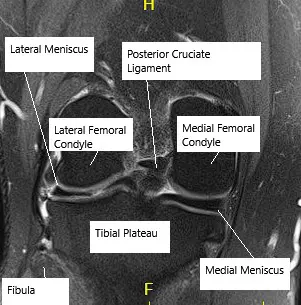

The knee joint is formed by the thigh bone above, the shin bone below, and the kneecap in front. Between the thigh and shin bone are two menisci—medial (inner) and lateral (outer). Each is a C-shaped fibrocartilage disc that helps absorb shock, spread load, support bending and rotation, and protect the joint surface.

The meniscus has good blood supply only on the outer edge. The inner part has almost no blood supply, which affects healing. The medial meniscus tears more often because it is less mobile and more firmly attached.

MRI showing knee meniscus.

A physical exam may show signs of a tear or other knee injuries. X-rays are done to rule out fractures or subluxations. An MRI is the test of choice because it confirms the tear and shows the tear pattern, which helps plan treatment.